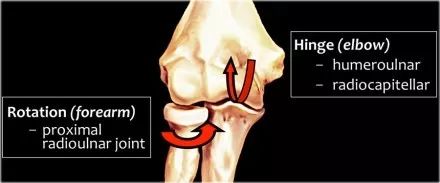

肘部作为铰链点,我们可以看到humeroulnar和radiocapitellar联合。另一个关节是近端桡尺关节,旋转允许内旋和旋后。